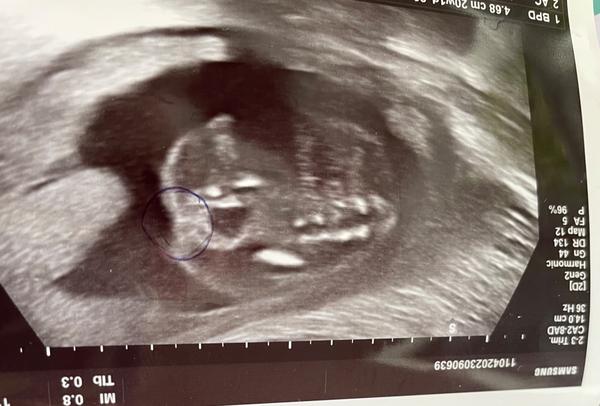

Chlapec nebo děvče?

chtěla bych se zeptat na pohlaví miminka.

Je možné rozpoznat z ultrazvukového snímku?

z těchto fotografií to odhadnout nelze, rovina řezu není ta správná. ☹